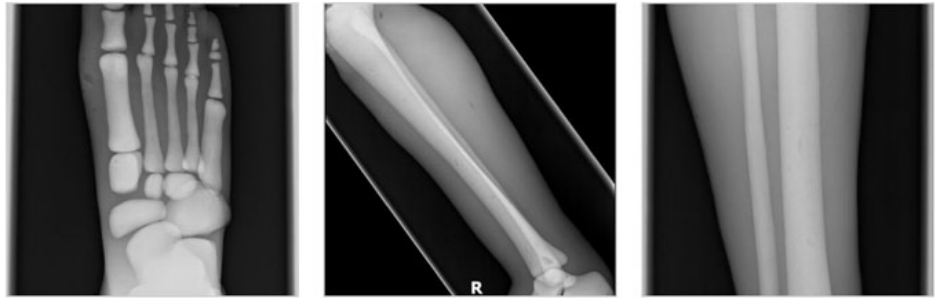

成人腿部模體,用于 X 射線 CT 和超聲波的成人腿部(肌肉)模型是一種基于人類男性腿部平均解剖結構設計的逼真模型。它具有所有基本的骨骼和

軟組織特征,使其成為學習、研究和測試醫學成像設備的理想工具。 模體可用于研究不同方向和定位技術的多種診斷性 X 射線 CT 和超聲程序。根據

要求,該產品可以根據不同的病理進行定制,也可以用于特定的培訓應用。 模體尺寸:965.2 x 254 x 177.8 毫米,重量:12kg(約)